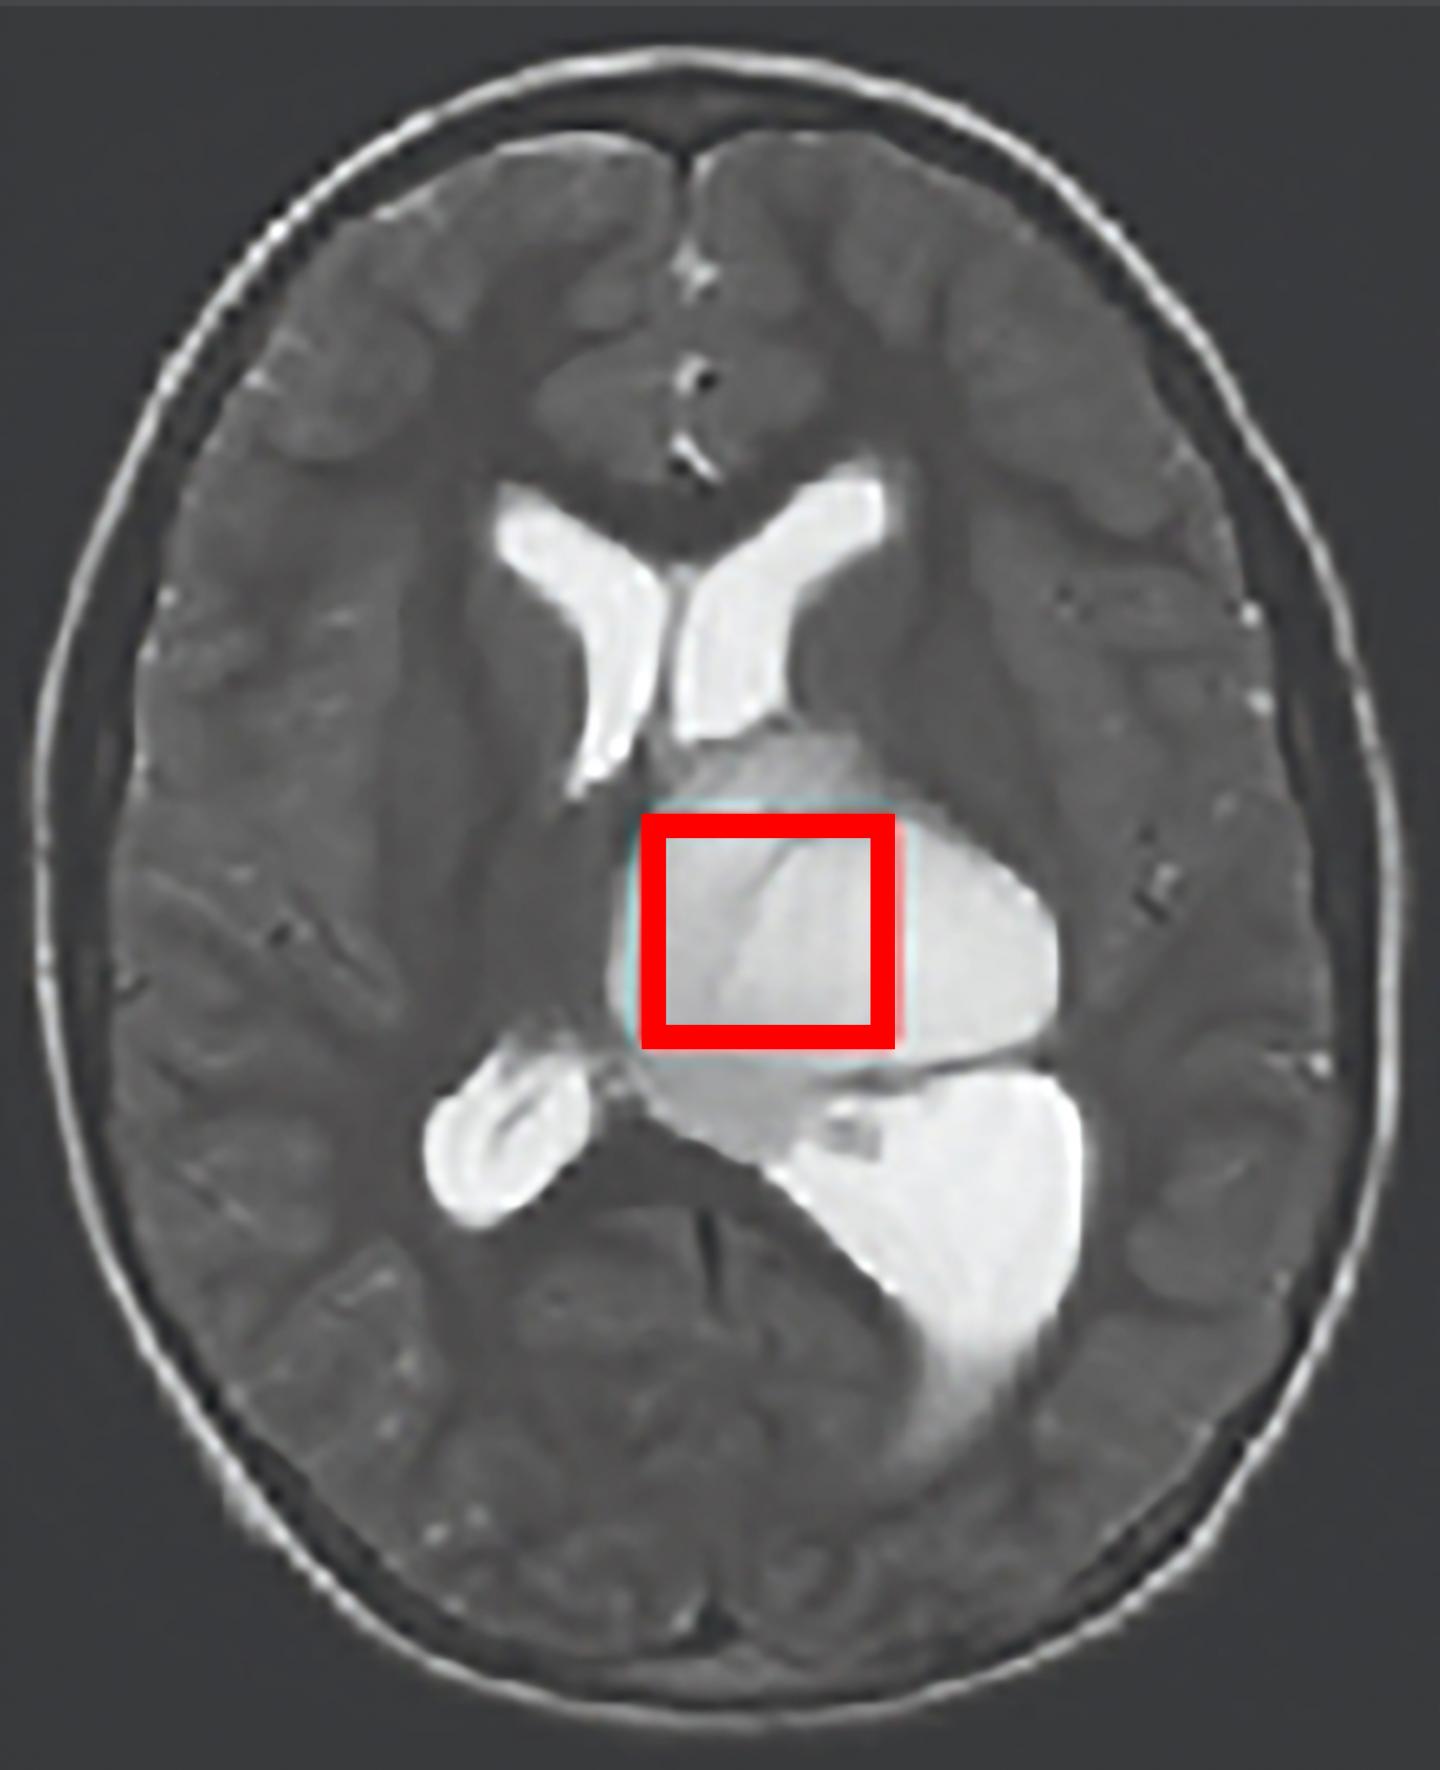

image: Brain scans of patients helped NIH funded researchers find that manipulating cancer cell metabolism may combat diffuse intrinsic pontine gliomas (DIPGs) and other tumors.

Brain scans of H3K27M patients showed that they had higher levels of certain precursor metabolites - namely glucose and glutamine - than patients with deep brain tumors who do not carry the H3K27M mutations. Then through a series of detailed experiments on mice and cells in petri dishes, the researchers found that H3K27M mutations induced the cancer cells to produce high levels of α-KG and this, in turn, spurred more growth. Further results suggested that this happened because α-KG prevented methylation of histones and thus epigenetically kept genes that are vital for cancer cells exposed and active. For instance, lowering α-KG levels with experimental drugs increased histone methylation, slowed cancer cell growth, and helped mice harboring the DIPG tumors live longer. In contrast, they saw surprisingly opposite results in lower grade tumors associated with mutations in isocitrate dehydrogenase genes (IDH1), which naturally produce lower levels of α-KG. Introducing H3K237M genes into IDH1 tumors slowed growth by raising alpha-ketoglutarate levels which, in turn, increased methylation and turned off cancer-sustaining genes. The researchers concluded that understanding the intricate details behind these feedback loops may help researchers devise effective ways to treat DIPG and other brain tumors.